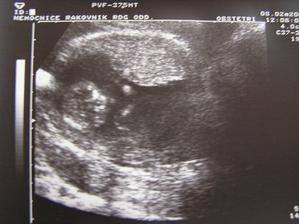

SRPŇÁTKA 2007 - fotky UTZ

album věnované mimískům, které se narodí v srpnu 2007 a jejich maminkám ze "Společného termínu SRPEN"